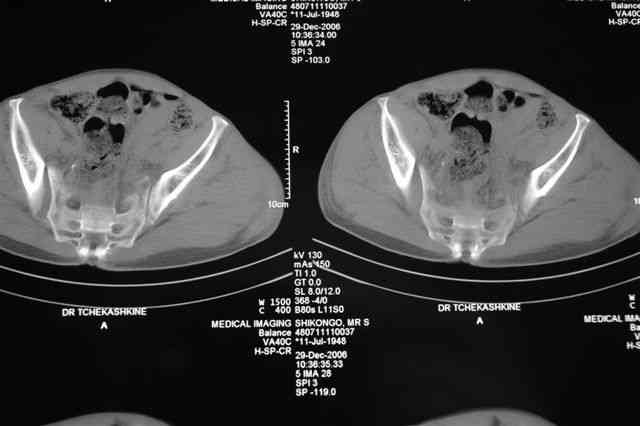

В приложении отправляю послеопер. снимки бедра и лодыжки обсуждаемого вчера больного.